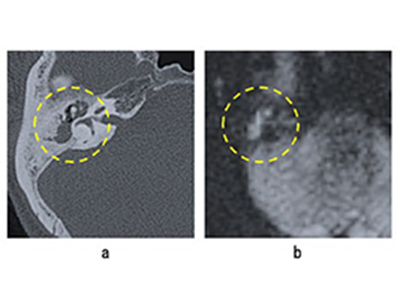

研究では、2011~2020年に東京慈恵会医科大学附属病院耳鼻咽喉科において、弛緩部型真珠腫に対して初回手術と治療前評価のための側頭骨CTを受けた164例(男性104例、女性60例、年齢層13~82歳、平均年齢[±SD]42.0±15.3歳)(右83 例、左81例)を対象とした。弛緩部型真珠腫の診断は術中所見および摘出組織の病理組織学的検査に基づいて行った。乳突腔進展を示す症例(M+)と進展を示さない症例(M-)の2群に分類したところ、80例と84例がそれぞれM+とM-に分類された。CTの閾値は骨条件で行い(window center:700、window width: 4000)、患者情報は削除し、水平断画像のみを用いて、上半規管の頭側から尾側方向に30スライスを抽出。そのうちDNNモデルの学習と評価のために病変部が含まれるスライスを抽出。患者を無作為に8グループに分け、学習用と評価用を分けて交差検証を行った。

学習時には、224×224ピクセルのサイズに切り出した画像を用いて、画像の病変部を範囲内に収めながらDNNモデルを学習させた。1つのDNNモデルの1回の学習サイクルでは、50回の反復学習を繰り返し実行。この学習サイクルを8つのデータセットで行い、1つの学習セットで8つのモデルを生成した(学習セット:評価セット=7:1)。各DNNモデルの学習は少数の患者からオーグメントで生成した大量のデータを用いるため、学習するたびに能力・精度に差が出る。その能力・精度の変動を検証するため、24の学習セットを作成した。その結果、8データセット×24=192個のモデルが生成された。

単一画像単位予測における最高の精度は25%画像に対するアンサンブル予測によって実行された際の75.43%(感度=77.12%、特異度=73.75%)だった。患者単位予測における最高の精度は、25%画像に対するアンサンブル予測によって実行された81.14%(感度=84.95%、特異度=77.33%)だった。この結果から、アンサンブル予測は単一モデルの予測よりも精度が良く、25%画像に対する予測は、元画像(100%画像)の予測よりも良い性能をもたらすことが明らかになった。

乳突腔進展とCT陰影の有無の正答率の差、耳鼻科医は15~20%、AIは10%以下

さらに、術中所見とCTの陰影が一致しているか否かによる違いは、耳鼻科医が65.1%(87.7-22.6%)、AIが33.2%(84.0-50.8%)だった。これらのことから、耳鼻科医は主に陰影の有無で判断しているがAIはそうではないこと、人間が判断しにくい症例でAIの方が正答率の高い症例があることが示唆された。一方、耳鼻科医が容易に診断できるがAIの精度が低い症例もあった。これは、耳鼻科医は乳突腔を明確に定義できることと、耳鼻科医にとって一般的な所見であっても、あまりにも著しい進展例でAIが初めて見る画像ではAIの十分な性能を発揮できないためと考えられるという。しかし、この点について研究グループは、症例数を増やすことで解決されると思っている。少ない症例数で高い精度のAIを作成できたが、今後はより大規模な多施設共同研究の施行が望ましいとしている。